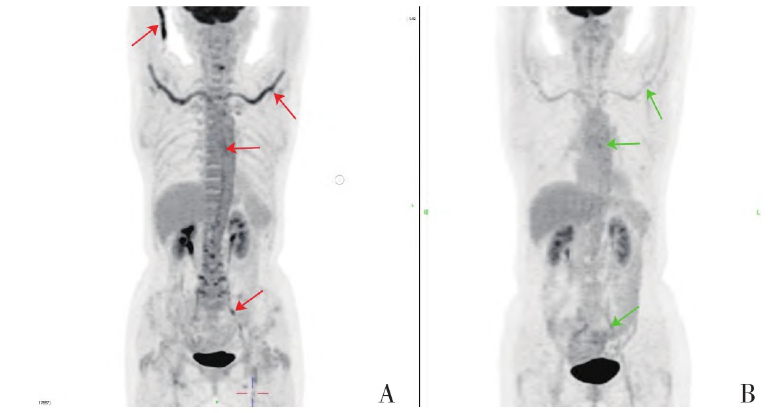

患者拒绝行动脉活检,18F-脱氧葡萄糖

正电子发射断层扫描(18F-deoxyglucose positron emission tomography,18F-FDG-PET/CT)示主动脉、双侧头臂动脉-锁骨下动脉-肱动脉、髂动脉及股动脉上段管壁弥漫性增厚,不均匀葡萄糖代谢增高(图2A、3A、3E),腰2-5双侧椎小关节、双侧坐骨结节周围及双髋关节周围软组织代谢异常增加(图3C、3E)。确诊为巨细胞动脉炎(giant cell arteritis,GCA),予醋酸泼尼松片(60mg,qd)治疗3d,患者乏力等症状明显改善。

2021年4月6日复查,查体见满月脸;白细胞5.11×109/L,C反应蛋白0.398mg/dl,ESR 11mm/h,Ig M26.1mg/dl;肝肾功能正常;血管超声(图1C、1D)示颞动脉“晕环征”消失;18F-FDG-PET/CT示:主动脉、双侧头臂动脉-锁骨下动脉-肱动脉、髂动脉及股动脉上段代谢较前减低(图2B),腰2-5双侧椎小关节代谢增高区消失,双侧坐骨结节及双髋关节周围软组织代谢减低,颈6椎体左侧局部高代谢消失(图2B、3B、3D、3F)。患者症状明显好转,食欲佳,体重增加约5kg。继续予醋酸泼尼松龙片(15mg,qd)口服治疗,每2周减少2.5mg。患者后未诉明显不适,规律复诊。

图2 治疗前后躯干18F-FDG-PET/CT影像(冠状面)。A.红色箭头示治疗前主动脉、双侧头臂动脉-锁骨下动脉-肱动脉、髂动脉及股动脉上段管壁弥漫性代谢增高;B.绿色箭头示治疗后上述动脉管壁代谢较前减低,颈6椎体左侧局部高代谢消失。